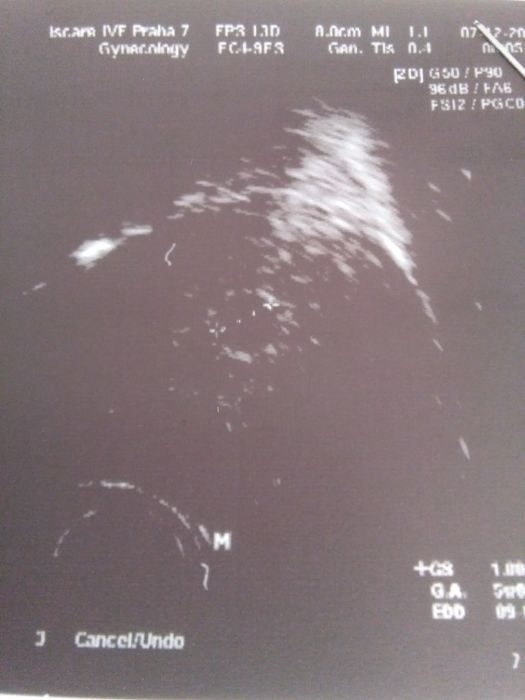

tak vyhráno není, zvýšili mi dávku utrogestanu na 6 denně, spočítali mi že bych dnes měla být podle ms 5+4(tady na kalkulačce mi to vychází 6+4 ???) , podle ultrazvuku je to 5+0 a je vidět zatím prý jen váček s tečkou a odpovídá to prý té inseminaci, kontrola za 10 dní, jdu 16.12 je to pátek a tam se rozhodne, takže bojim bojim...